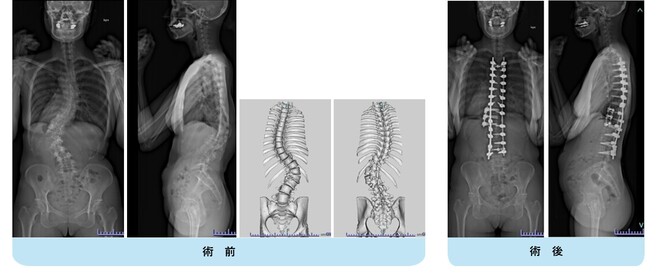

思春期特発性側弯症の全脊椎レントゲンで背骨が大きくSの字に曲がっています。最も曲がっている箇所は80°で、高度側弯に分類されます。後方からの脊柱側弯矯正術で真っ直ぐになっています。

また、側弯の患者さんは一般的にフラットバックと言って背骨の生理的後弯(背中の丸み)が失われています。この症例も胸椎後弯角は5°で典型的なフラットバックを呈しています(正常は20°~30°程度です)。この影響は頸椎の形態にも影響を及ぼし、この症例も頸椎が既に後弯(正常は前弯)しています。(黄色矢印)

ストレートネックという頸椎の前弯が消失して頸部の愁訴が出現する病態は広く知られていますが、更に変形が進行した頸椎と考えて下さい。

以前はこのフラットバック(生理的胸椎後弯の消失)を治すことは困難でしたが、当院では手術方法の様々な工夫により生理的胸椎後弯の復元を行っております。この症例は術後に胸椎後弯角が26°と改善しており、生理的な胸椎後弯が形成されています。さらに頸椎後弯にも良い影響を及ぼし、術後は頸椎前弯化が得られつつあるのが分かります。(黄色矢印)

他、側弯変形は必ず大なり小なりの回旋変形を伴います。脊柱の回旋変形は胸郭(肋骨)の回旋につながり、これにより側弯の患者さんは背中の片方が出っ張っています(多くは右)。リブハンプと言いますが、脊柱変形矯正によりこの回旋変形も改善します。この症例も術前に肋骨がかなり隆起していますが、術後にこの隆起がかなり減じているのが分かります。(赤矢印)